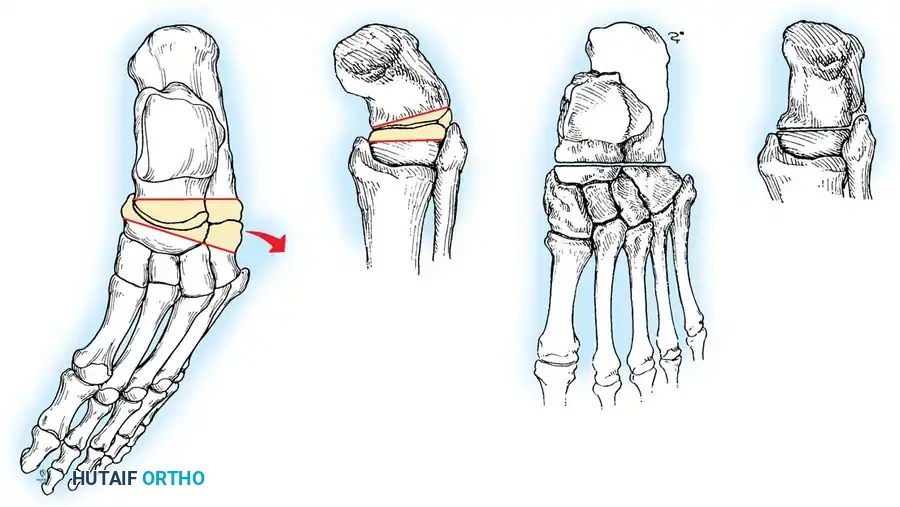

1. First Metatarsal Dorsiflexion Osteotomy

* Indications: Rigid plantarflexed first ray.

* Approach: Dorsal longitudinal incision over the proximal first metatarsal.

* Osteotomy: Protect the extensor hallucis longus (EHL) tendon. Perform a dorsal closing-wedge osteotomy approximately 1.5 cm distal to the tarsometatarsal joint.

* Fixation: Elevate the metatarsal head to neutral alignment with the lesser metatarsals. Fixate with a dorsal titanium plate, crossed K-wires, or a compression staple.

Fig. 8: Planning the dorsal closing wedge osteotomy of the first metatarsal to correct forefoot equinus.